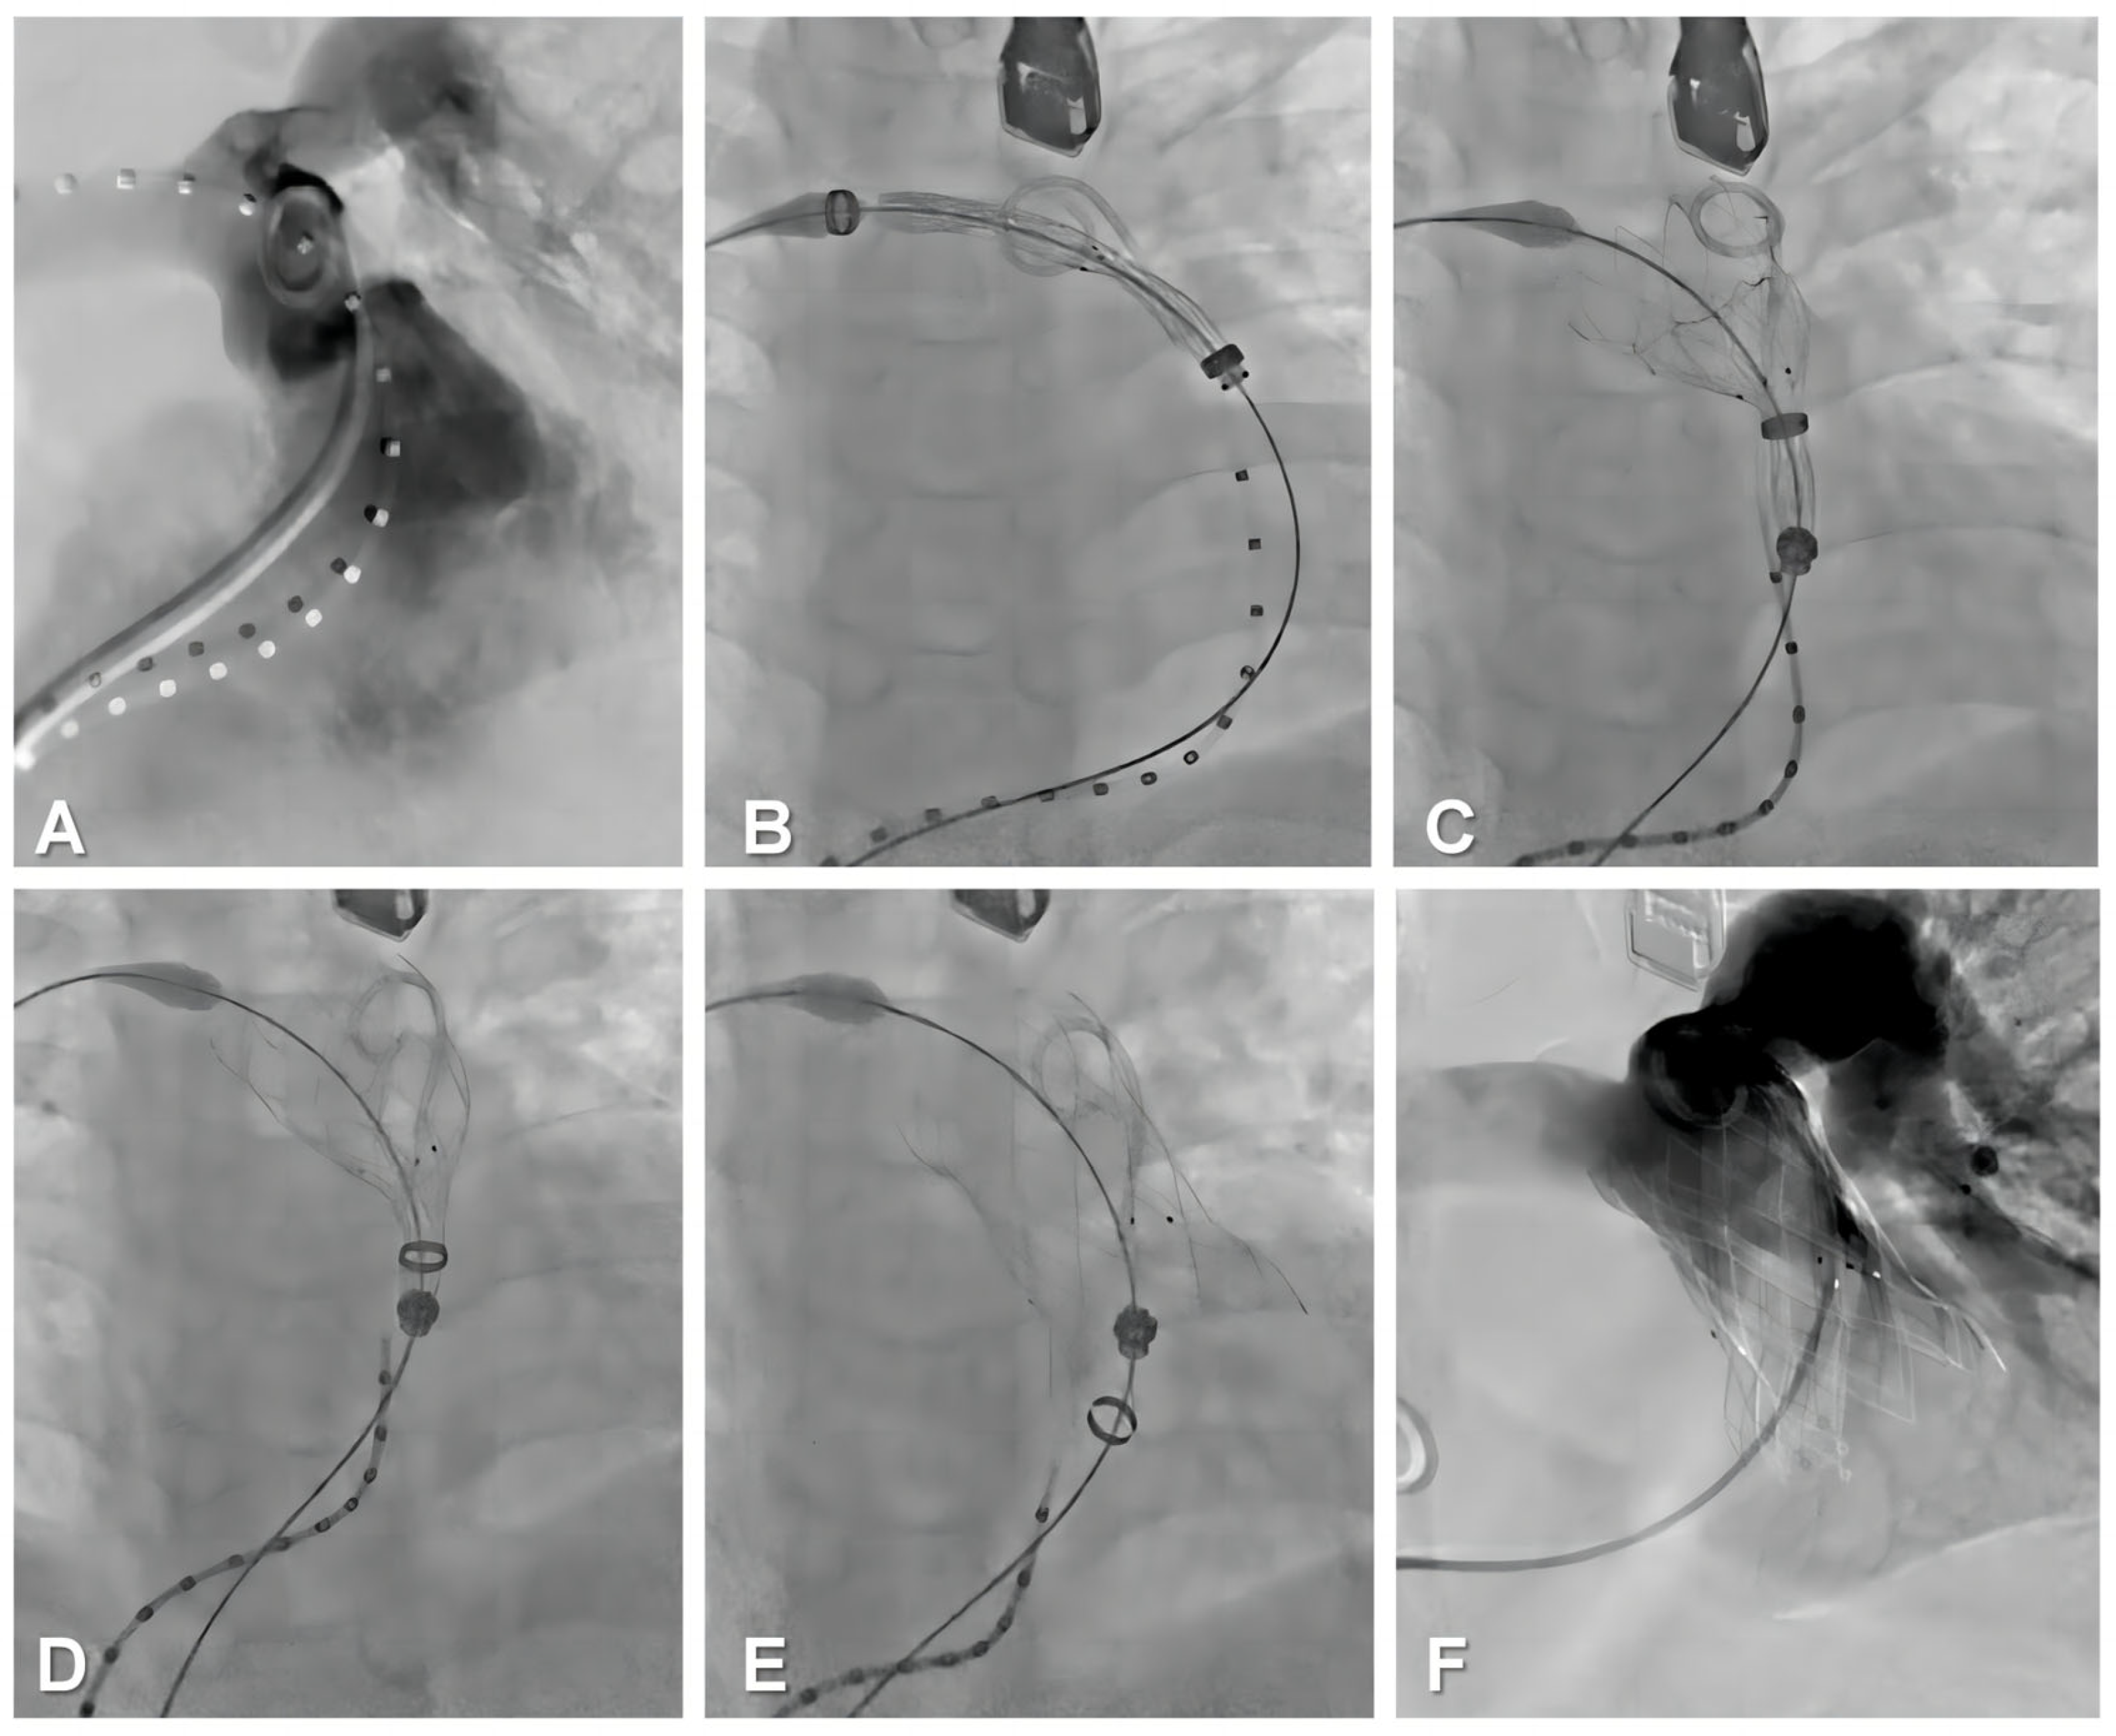

2.5. Procedural Steps